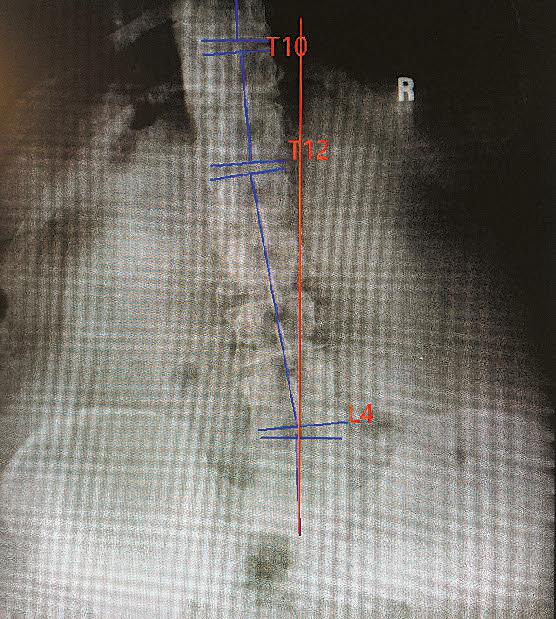

The nervous system controls and coordinates all functions of the body, making its proper functioning essential for overall health. Structural shifts in the spine can obstruct the nerves and interfere with their function. Chiropractors refer to these obstructions as vertebral subluxations, and they are at the core of chiropractic care.

Find out if subluxations are affecting your health with a chiropractic examination with any necessary x-rays for just $59 this month at any Crossroads Chiropractic location.